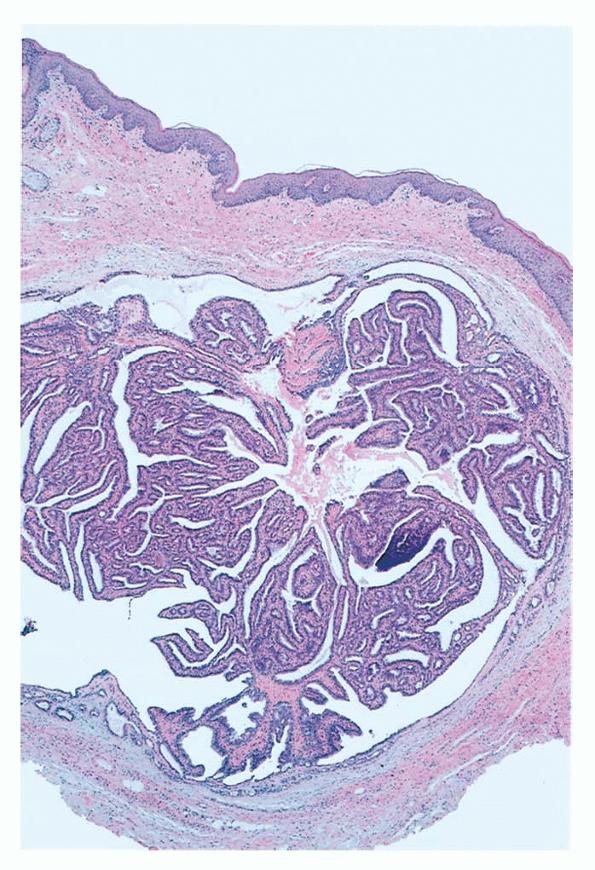

Hidradenoma papilliferum = الغدوم العرقي الحليمي